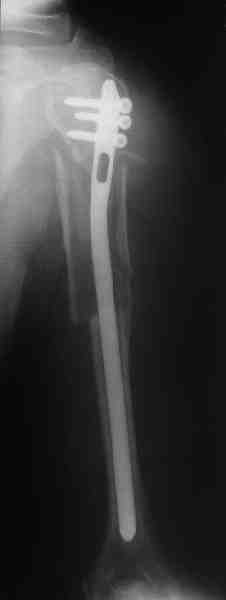

Уважаемые коллеги.

Прооперировали больную с переломом плеча все же гвоздем, Фото в приложении.

Re: Оскольчатый перелом плеча

Отправитель: Никита Заднепровский 20 Август 2006, 22:38

Интересно, а канал рассверливали?

Гвоздик похоже ЦИТОвский?

Полагаю, бабушку можно поздравить с обретением

независимости. Судя по снимкам, неврологических расстройств нет и такая пациентка выпишется после снятия швов.

Какие рекомендации Вы дадите этой женщине на ближайшие 6 месяцев?

Отправитель: Alexaander Chelnokov 20 Август 2006, 23:36

|

Только сформировали канал в головке. Диафиз не рассверливали. Хотя при необходимости, конечно, рассверлили бы.

НЗ> Гвоздик похоже ЦИТОвский?

Гвоздь большеберцовый нашей модификации, действительно, их делает предпричятие "ЦИТО". Тут взят 9 мм, укорочен до 240 мм, сделано дополнительное отверстие самое проксимальное, ну и для дистального винта.

Неврологии нет, а выписать можно хоть на второй день, швы можно снять и в местной больнице.

Почему так надолго? На ближэайшие недели - разработка движений, и все. Полагаю, что недель после 4 никаких рекомендаций не будет нужно, просто жить обычной жизнью сельской пенсионерки.